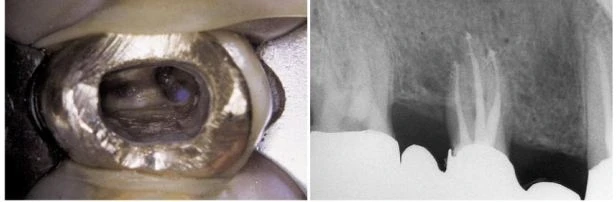

Nghiên cứu gần đây của John Stropko rất thú vị, ông cho rằng ống tủy thứ hai của chân ngoài gần tồn tại ở nghiên cứu “in vivo” trong 93% trường hợp và có thể đánh giá được lỗ chóp của nó trong 90% trường hợp. Stropko, trong một bài báo của ông, có viết rằng tỉ lệ % ông tìm thấy cao như vậy là nhờ ứng dụng kính hiển vi phẫu thuật và trong một vài trường hợp rất khó, có thể nói rằng không thể quan sát được miệng MB2 nếu không dùng kính hiển vi phẫu thuật. Một điều thú vị rằng là sử dụng kính hiển vi phẫu thuật nghiên cứu thì tỉ lệ % hiện diện MB2 cao hơn khi nghiên cứu mà sử dụng những phương tiện khác. Miệng của ống MB2 – nên gọi tên là ống tủy gần trong – nằm trong rãnh nối giữa ống trong và ống gần ngoài (hình 11.59 A, B). Để tìm MB2 ta có thể tìm một chỗ lõm nhỏ trên rãnh nói trên, tại điểm này cây thám trâm nội nha bị giữ lại. Tuy nhiên đôi lúc thám trâm không đi vào được vì thành gần của buồng tủy tạo một góc rất nhọn với sàn tủy và cản trở tầm nhìn, cũng như là thám trâm không chạm được vào miệng ống tủy (hình 11.59 C). Thành gần của buồng tuỷ có một gờ ngà che đi miệng của MB2 nằm bên dưới nó (hình 60A). Vì góc này, MB2 rất khó đánh giá. Trong 1-3mm đầu, ống tủy nghiêng 1 góc nhọn về phía gần, đây là lý do vì sao đầu trâm không thể tiến về phía chóp hơn một vài mm và nó bị dừng lại tại thành gần. Vì vậy trước khi tiến hành đánh giá ống tủy này cần mở góc này đi để loại bỏ gờ ngà trên thành gần xoang tủy, tạo một đường vào thẳng đến ống tủy. Điều này có thể thực hiện được dễ dàng, an toàn và hiều quả bằng máy siêu âm, chẳng hạn với đầu CPR và ProUltra (hình 11.60B). Nếu nhà lâm sàng loại bỏ gờ này bằng trâm thay vì dùng máy siêu âm thì hình dạng miệng MB2 sẽ như trong hình 11.59D.

Hình 11.59. A. Xoang tủy của răng cối lớn thứ nhất hàm trên. Chú ý rãnh chạy bắt đầu từ miệng ống gần ngoài hướng về ống trong. B. Rãnh này sau khi làm sạch và tạo hình ống gần trong. Chỗ lõm phía xa cũng được mở bởi một mũi khoan tròn nhỏ vì nghi ngờ có ống xa trong. C, D. Hình vẽ cho thấy góc giữa sàn tủy và gờ ngà ở thành gần xoang tủy (Courtesy of Dr. S. Buchanan). E. Hình dạng miệng ống tủy gần trong nếu gờ ngà không được loại bỏ bằng máy siêu âm.

Hình 11.60. A. Ảnh chụp với độ phóng đại 12 lần bộc lộ miệng của ống gần ngoài và rãnh liên quan. Một gờ ngà che đi miệng ống tủy bên dưới. B. Sau khi mở một đường vào thẳng, dùng đầu siêu âm thích hợp loại trừ gờ ngà một cách dễ dàng và an toàn, bộc lộ miệng ống tủy gần trong (Courtesy of Dr. C.J. Ruddle)